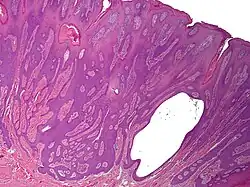

Syringofibroadenoma

Syringofibroadenoma is a cutaneous condition characterized by a hyperkeratotic nodule or plaque involving the extremities.[1]: 668

It is considered of eccrine origin.[2]